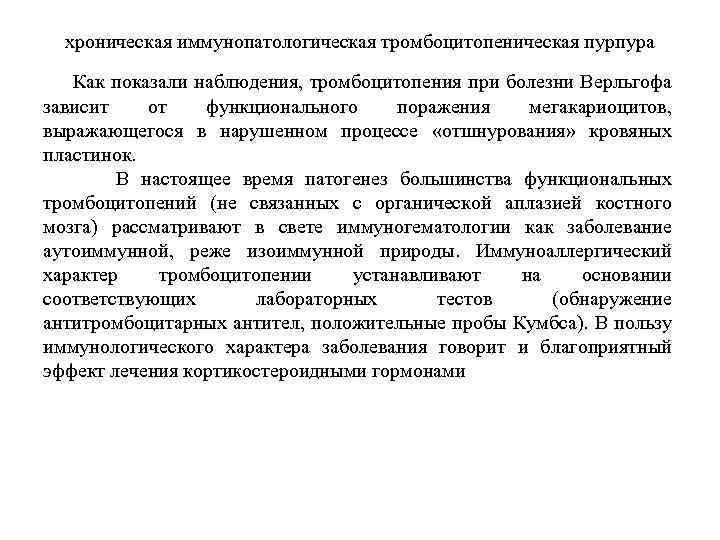

хроническая иммунопатологическая тромбоцитопеническая пурпура Как показали наблюдения, тромбоцитопения при болезни Верльгофа зависит от функционального поражения мегакариоцитов, выражающегося в нарушенном процессе «отшнурования» кровяных пластинок. В настоящее время патогенез большинства функциональных тромбоцитопений (не связанных с органической аплазией костного мозга) рассматривают в свете иммуногематологии как заболевание аутоиммунной, реже изоиммунной природы. Иммуноаллергический характер тромбоцитопении устанавливают на основании соответствующих лабораторных тестов (обнаружение антитромбоцитарных антител, положительные пробы Кумбса). В пользу иммунологического характера заболевания говорит и благоприятный эффект лечения кортикостероидными гормонами